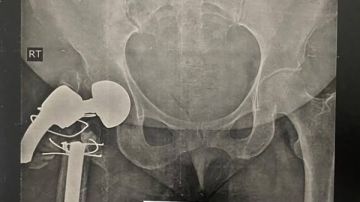

إنجاز طبي جديد يُضاف إلى سجل نجاحات مستشفى الهلال الأحمر في جراحات العظام حيث استقبلت مستشفى الهلال حالة دقيقة لسيدة تبلغ من العمر 57 عامًا، تعرّضت لحادث نتج عنه كسر في مفصل صناعي بالفخذ الأيمن، مصحوب بتآكل شديد في الجزء العلوي من عظمة الفخذ.

وقد نجح الفريق الجراحي في إجراء عملية دقيقة، تم خلالها استئصال المفصل التالف، وزراعة مفصل صناعي جديد مزوّد بجزع خاص يُستخدم في حالات الأورام أو الجراحات المعقدة لإعادة الاستبدال، وتم اختياره بعناية ليتناسب مع طبيعة الحالة.